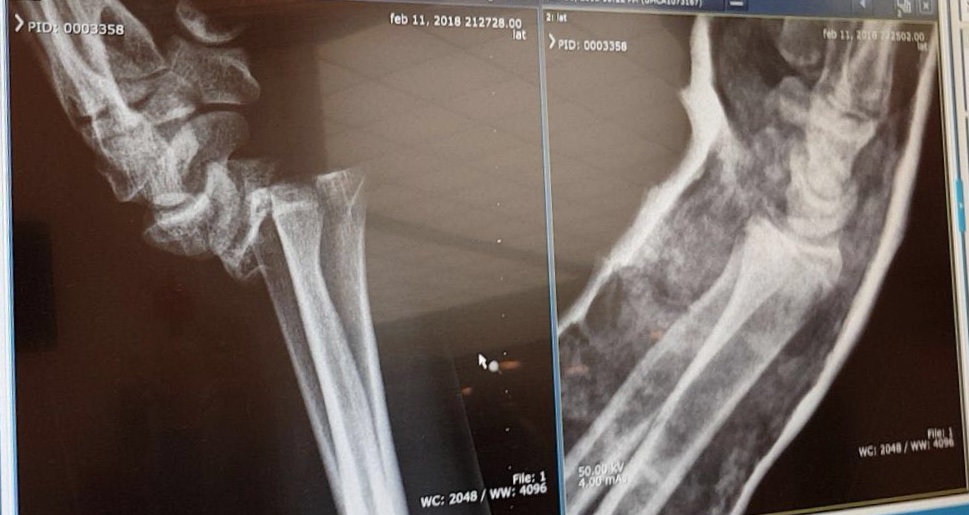

Op de röntgenfoto is goed te zien dat de pols gebroken is. Vijf weken gips is wat de Oranje U20 international staat te wachten. Vervolgens kan het herstel beginnen. Vandaag had Donny Pohlman nog veel last van zijn pols, maar hij is vol goede moed over zijn herstel. Face-Off wenst hem hierbij veel sterkte.